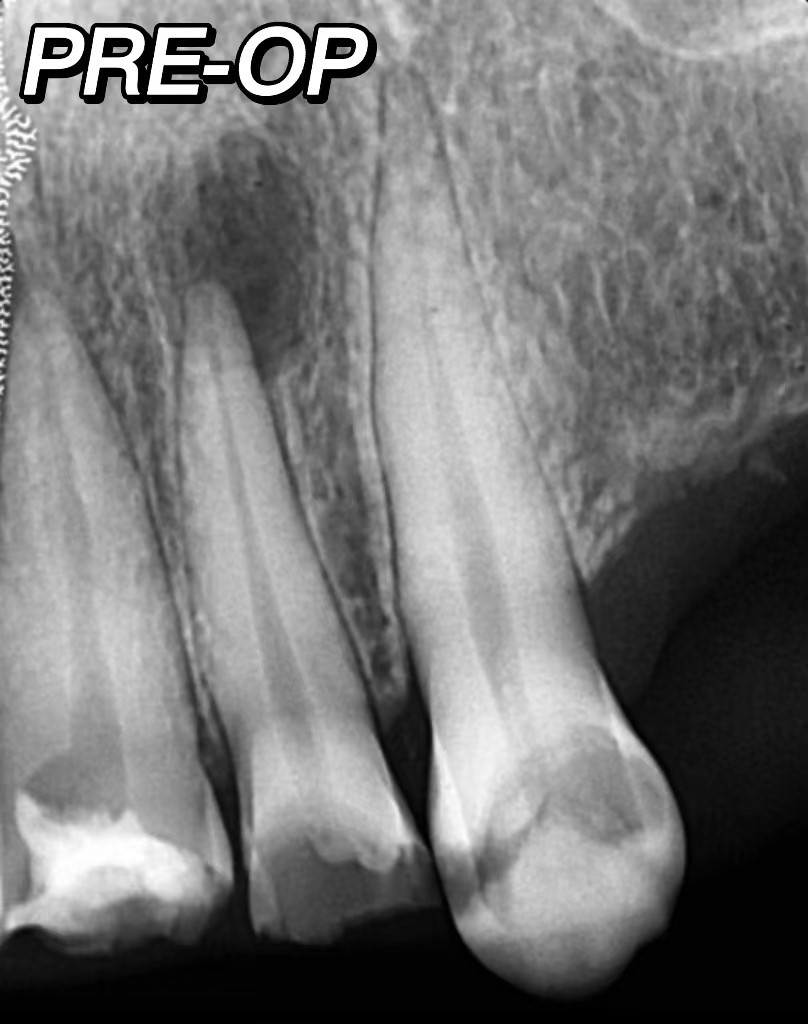

RCT of upper lateral incisor as a part of complete oral rehabilitationUsing Videya Dental TC Blue fies